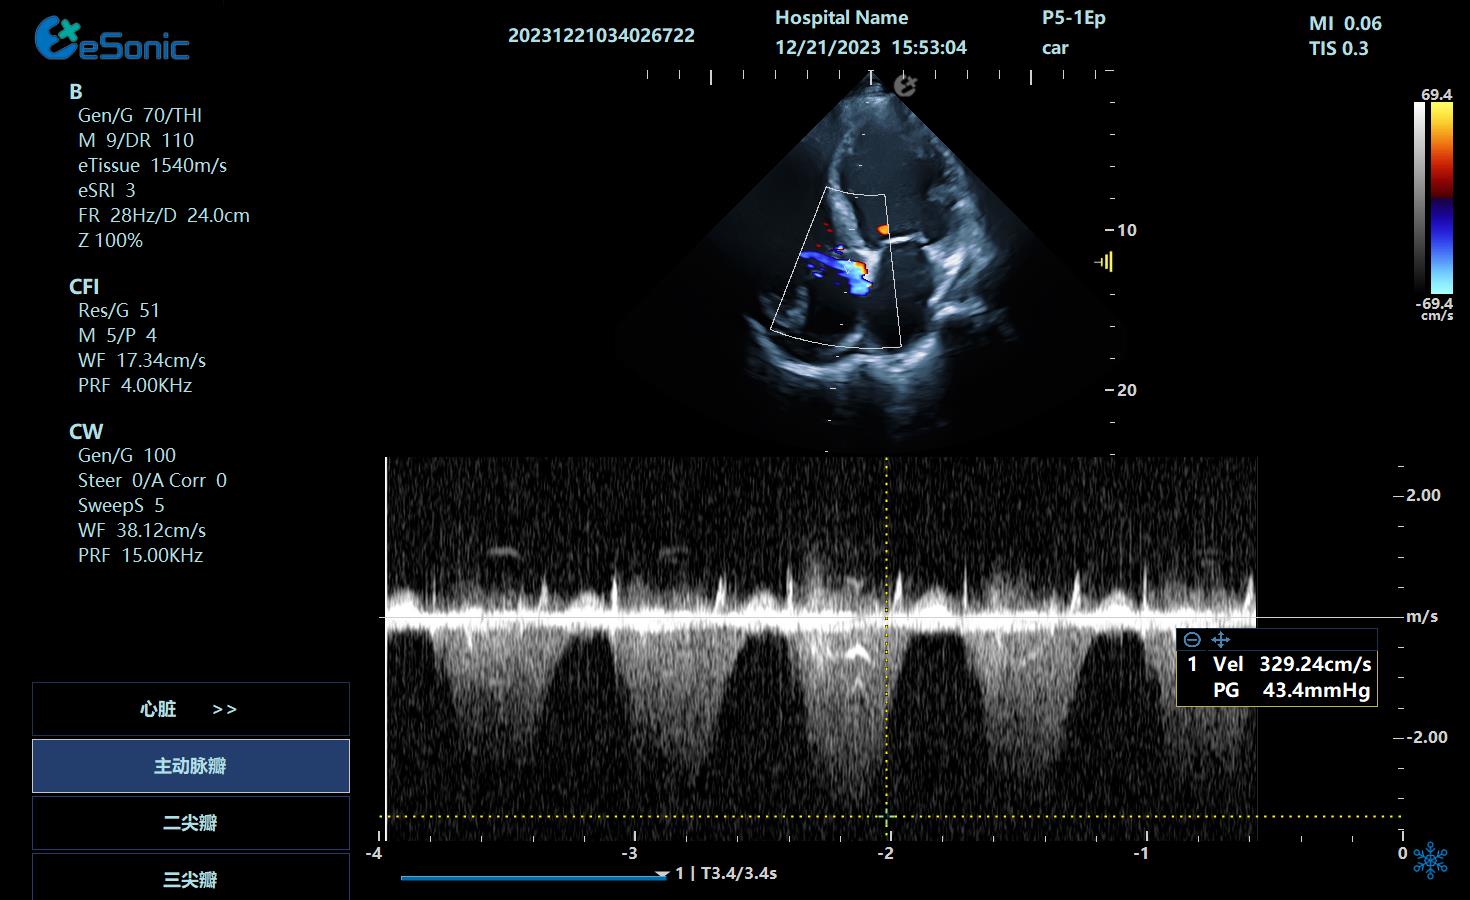

心尖四腔心

三尖瓣返流